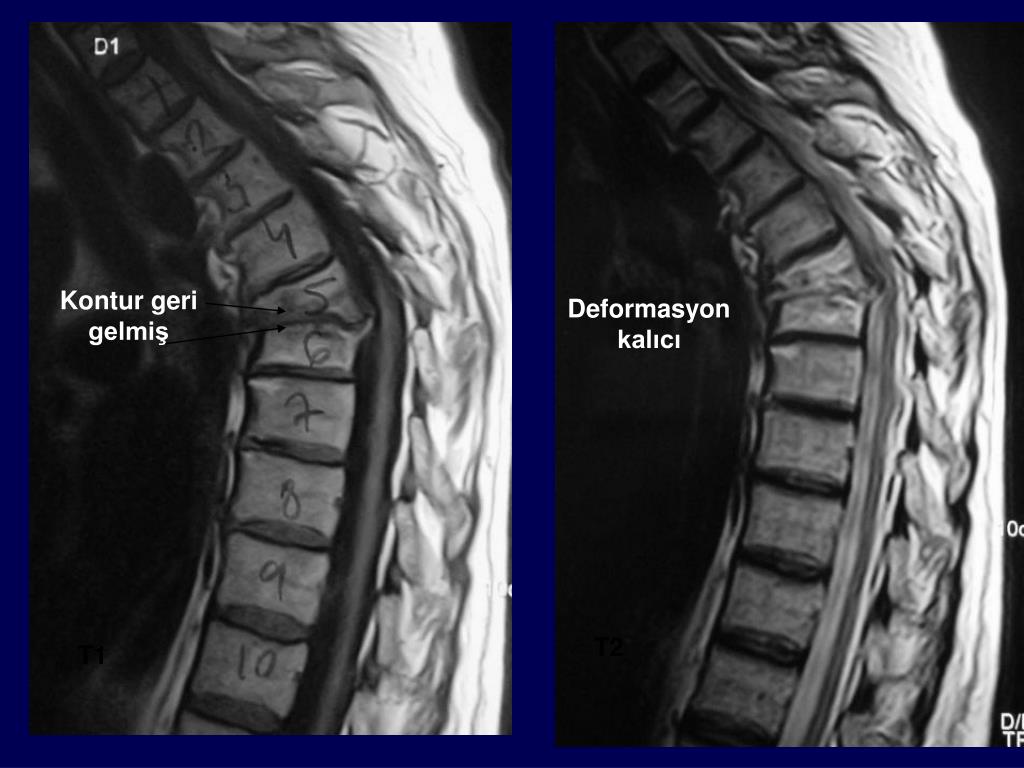

18. Kontur geri gelmiş Deformasyon kalıcı T2 T1